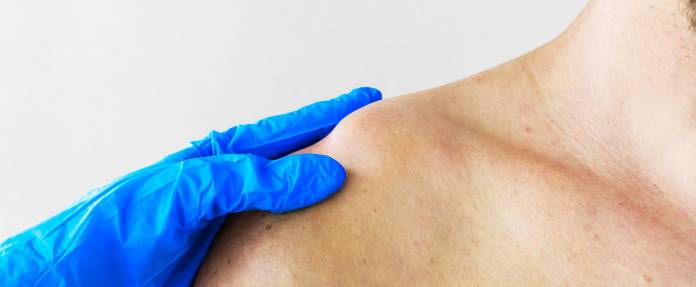

Bereits in der klinischen Untersuchung kann der Arzt eine Schulterluxation feststellen. Dabei sind folgende Symptome typisch:

Typische Symptome einer Schulterluxation sind schmerzhafte Bewegungseinschränkung, eine als Delle tastbare leere Gelenkpfanne oder eine fixierte Stellung des Arms (oft nach außen gedreht vom Körper weggestreckt). Wichtig ist, das Schultergelenk so schnell wie möglich in die korrekte Position zu bringen, um Folgeschäden zu vermeiden.